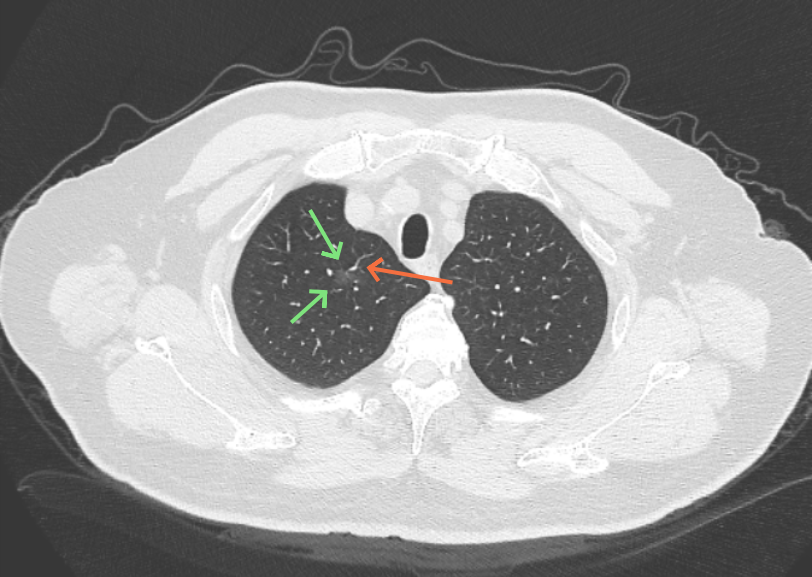

影像展示与分析:

病灶B似乎灶内有少许密度略偏高,但瘤肺边界欠清晰,总体说不上太显著的进展。

当时结友自己还觉得有点实性成分,血管感觉也有增粗。而我觉得整体密度仍是磨玻璃,轻微的变化仍不足以影响临床决策的程度。

病灶没有确切纵隔窗可见的实性成分,但与血管关系较为密切。